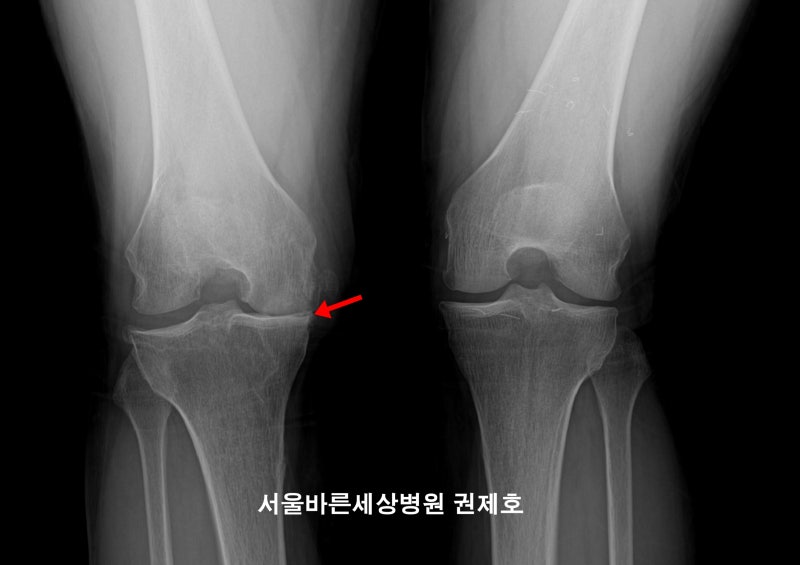

관절염은 주로 무릎 안쪽에서 진행되며 다리의 축이 비스듬해지면서 이른바 ‘O다리’가 된다. 축이 곧지 않으면 체중을 균등하게 분산시키는 뼈의 무게를 늘리는데 노화 또는 사고로 인해 축이 무너지게 되면서 연골이 닳는 속도는 빨라지고, 즉 관절염 진행 속도가 빨라지는 것이다. 근위골절골술 수술 과정

관절염은 주로 무릎 안쪽에서 진행되며 다리의 축이 비스듬해지면서 이른바 ‘O다리’가 된다. 축이 곧지 않으면 체중을 균등하게 분산시키는 뼈의 무게를 늘리는데 노화 또는 사고로 인해 축이 무너지게 되면서 연골이 닳는 속도는 빨라지고, 즉 관절염 진행 속도가 빨라지는 것이다. 근위골절골술 수술 과정근위경골절골술의 수술 과정 설명은 꽤 간단하다.경골근위부를 절골하여 다리의 축이 ‘일자형’이 되도록 적합한 정도의 공간을 열어 뼈 모양을 교정시킨다.(왼쪽 그림) 그 후에 행해진 각도에 금속판을 이용하여 견고하게 고정하고 뼈의 유합 촉진을 위해 뼈 이식을 실시한다. (오른쪽 그림) 빈 공간 속 뼈가 생성되면서 일반 다리로 회복되는데 설정한 각도에 따라 다리 축을 변경하는 것이다. 오다리교정술이 필요한 경우 (굽은 다리교정술 조건)휜 다리 교정술(근위 경 골절술)에는 몇가지 조건이 있다.나는 중기 관절염이다.초기 관절염은 약물, 이학 요법을 쓰는 말기 관절염의 경우는 무릎 연골이 다 닳아 바꿀 경우이다.휜 다리 교정술은 초기와 말기 사이의 중기, 연골이 아직 있을 때 가능하다.내 발은 내 반 변형이다.O다리 시게루형에 의해서 안쪽 연골의 마모가 심해축이 변형된 사람의 때에 적당한 수술이다.저의 안쪽 외 관절(밖)는 아직 괜찮다.안쪽 관절염이 진행되고 O다리에 커지며 이때 교정 수술을 하는데 이때 외측은 문제가 있어서는 안 된다.저는 관절염이 비교적 일찍 시작한.100세 때 라키에 관절염이 비교적 일찍 시작, 향후의 관절을 보존하고 싶은 사람 50~60세의 나이가 적당하다.나는 두 다리를 더 자유롭게 사용하고 싶다.말기 관절염이 되면 인공 관절을 대체하게 되지만 인공 관절들은 아무래도 불편이 있다.그러나 오다리 교정술의 경우, 핀을 꽂아, 뼈 자체를 새로 생성시키고 핀을 제거하기 때문에 최종적으로는 자신의 관절을 보존한다.그래서 불편이 없다, 보다 활동적인 생활을 보낼 수 있다.줄기 세포 이식술 동시 수술이 가능(연쇄 시스템)근위경골절술을 진행하면서 마모된 관절에 줄기세포를 도포해 연골 스스로 재생할 수 있도록 하면 시너지 효과가 더 커진다. ※줄기세포이식술(카테스템) 줄기세포이식술은 재생효과가 좋은 아기의 제대혈에서 나온 혈액인 제대혈에서 유래한 줄기세포를 다량 함유한 치료제를 손상된 연골에 발라 연골재생을 유도하는 수술이다. 근위경 골절술 재활근위경골절골술은 절골 부위가 골유합(골생성)돼야 완전한 체중부하보행이 가능하다. 수술 후 1~2일째부터 바로 목발 보행을 시작한다. 수술 후 6주간 목발 및 보조기 사용이 필요하다. 수술 후 812주 후부터 가벼운 운동 복귀가 가능하다. 모든 과정은 최소 3개월 정도의 시간이 필요한 수술이다.이 과정 중 뼈가 물고기가 되는 것이 가장 중요하므로 이를 혈관 수축 효과가 있는 담배는 절대 금물이다. 서울원병원만의 구부러진 다리교정술의 특별함(가장 중요)특허받은 한국형 근위경골절술용 금속판 개발의 휘어진 다리교정술에 사용되던 기존 금속판은 서양인 체형에 따라 개발돼 한국인 체형에는 맞지 않고 이물감 및 통증이 남는 경우가 많았다. 이영민 서울원병원 대표원장은 이를 보완해 서울대병원 정형외과 의료진과의 공동연구로 한국인 체형에 맞는 금속판을 개발해 보다 만족스러운 수술 결과를 얻게 됐다.근위경 골절술 분야에 대한 끊임없는 연구서울원병원 나영곤 대표원장은 사체실험을 통한 근위경 골절술 연구의 우수성을 인정받아 국제학술지 논문 게재와 함께 서울대 의과대학 박사학위를 취득하고 다수의 관련 논문을 국제학술지(SCI)에 발표했다.수술을 할 수 있는 조건을 충족하는 사람이 근위경골절술을 통해 축을 수정해 관절염 촉진을 막을 수 있다고 한다.또한 이 수술을 통해 오다리가 일직선 다리로 예쁘게 자라기 때문에 다리 길이도 1cm 내외로 늘어나는 미용 효과도 얻을 수 있다는 점은 참고하기 바란다.나영곤 원장의 굽은 다리 교정술 유튜브 링크와 함께, 이제 근위경 골절술 포스팅 종료! https://youtu.be/cFl05f1PIm8#서울원병원 #근위경골절골술 #구부러진다리교정 #오다리교정 #카테스템 #강서구근위경골절골술 #강서구오다리교정 #강서구카티스템#연골재생#무릎줄기세포#강서구성형외과#화곡역정형외과#무릎통증#무릎수술#오다리교정비용#구부러진다리교정비용 #오다리교정수술비용